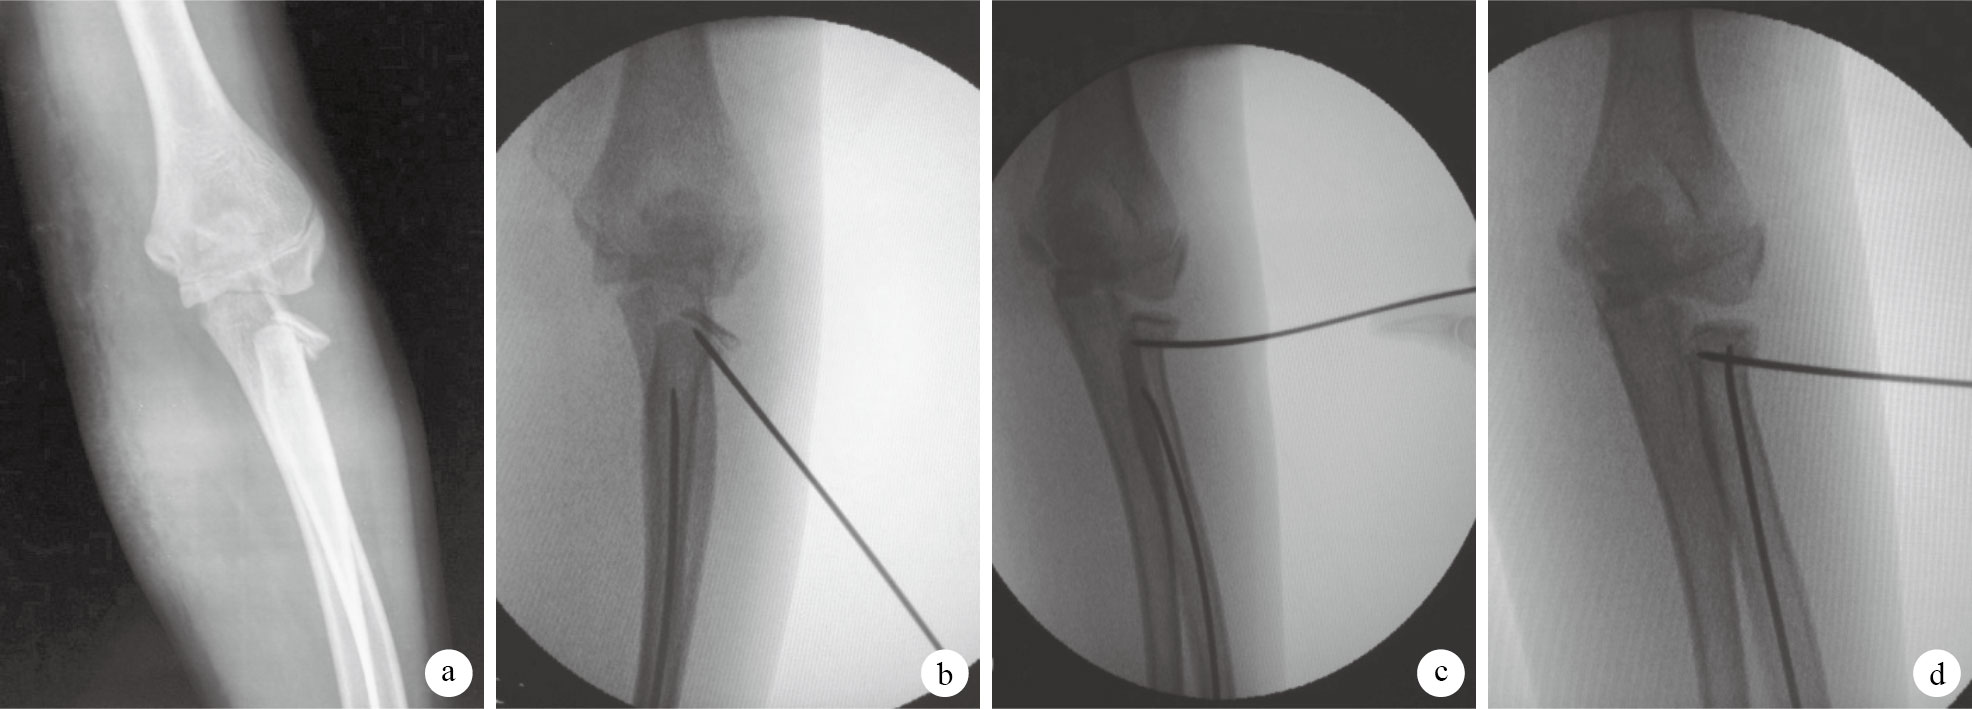

患兒全麻后取仰臥位,臂外展位放置于C臂X線機接收器上。于橈骨遠端橈背側距骺板1~2 cm處作一長約1 cm的縱切口,分層切至骨膜,避免損傷橈神經感覺支。開孔器先垂直于橈骨皮質開孔,再斜向近端將方向改為與橈骨長軸成30~45°角以擴大進釘骨孔;將預彎的彈性髓內釘安裝于手柄上插入骨孔進入髓腔,C臂X線機監視下,自肘關節外后下方將1枚2.0 mm或2.5 mm克氏針平行于手術臺面,經皮斜行向上插入至成角移位的橈骨頭外側骨骺下方;感覺克氏針觸及橈骨頭后,先將其向近端部分頂起使克氏針能夠插入至骨折斷端間隙,肘內翻使肱橈關節橈側間隙擴大;此時再以遠端骨折面作為杠桿支點,橈骨頭外側皮質為受力點向上撬撥,糾正成角及側方移位。復位滿意后,克氏針維持復位狀態,繼續推入彈性髓內釘,使髓內釘尖端進入骨折近端的骨髓腔并緊貼骺板彈性固定。見圖 1。本組4例經撬撥后骨折未能完全復位,再通過輕微旋轉髓內釘,糾正剩余成角或側方移位。固定滿意后釘尾折彎剪斷,保留0.5 cm于骨皮質外以便拔除。切口縫合1~2針。合并其他部位骨折作相應治療。